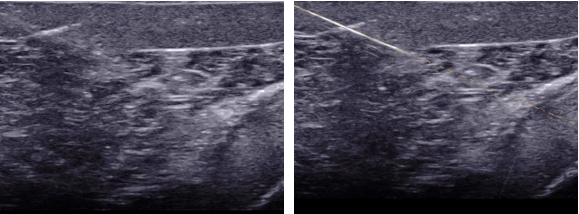

介入超声是在超声引导下将穿刺针、导管等医疗器具准确的进入靶目标从而达到诊断和治疗的一种手术手段,介入超声包括细针穿刺活检(FNA)、置管引流、囊肿硬化、结节的热消融。超声引导下穿刺介入手术就是在超声仪器检测下可直接观察到病灶目标,定位后将穿刺针对准靶目标后进行抽吸,如抽取肿瘤的实质是行组织或细胞的活检,胸水、腹水抽吸是实行抽液治疗。穿刺方法分为平面内穿刺和平面外穿刺,平面内穿刺是指沿探头长轴方向的穿刺A图所示,平面外穿刺是指探头短轴上的穿刺B图所示。

A平面内穿刺                                  B平面外穿刺